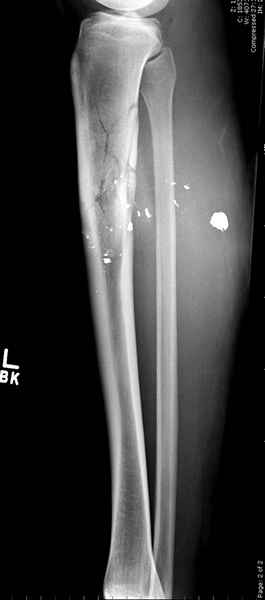

1 неполный перелом большеберцовой кости перкутанная пластина

2 перелом бедра